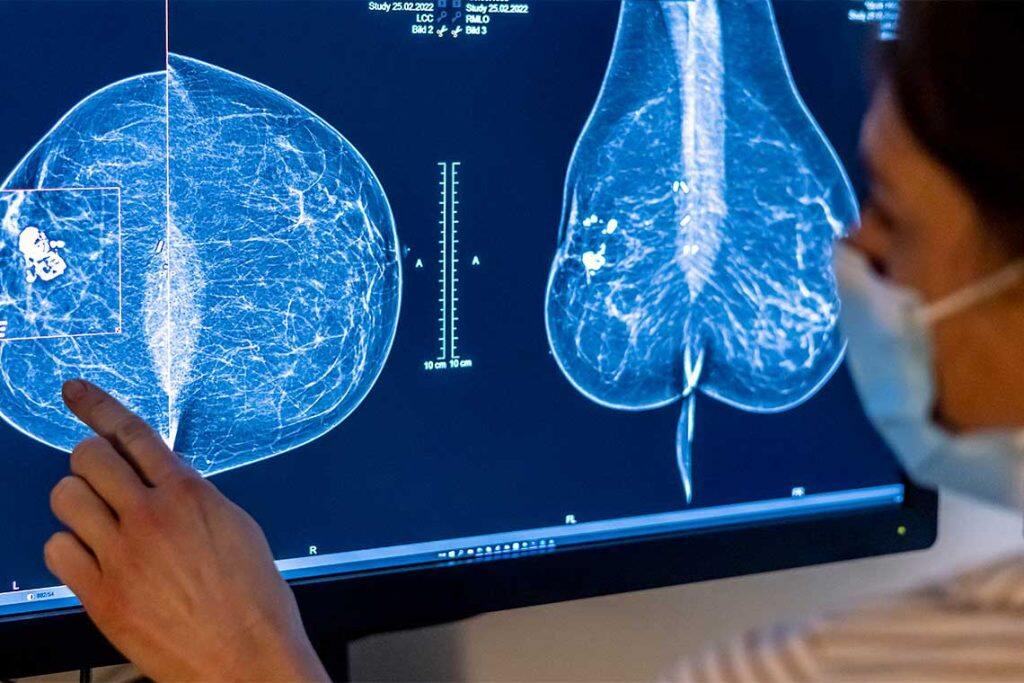

An international team of researchers have discovered a new genetic mutation that could help predict the likelihood of hereditary breast cancer.

For the other third, there has been no test to help members make decisions about how to protect themselves with procedures like preventative mastectomies.

Akbari and his colleagues sequenced the genomes of about 500 Polish breast cancer patients, plus a control group, and validated the preliminary findings with more than 25,000 breast cancer patients and controls from Poland. He found his smoking gun: a genetic mutation associated with more than a 100 per cent increased risk of breast cancer in the women studied. But the risk estimation was based on a single founder mutation in a gene known as ATRIP. Next, they searched for the mutations in the UK Biobank, which contains half a million genomes from a more diverse group of people. In that population, the relationship between the mutation and the likelihood of developing breast cancer was even stronger – more than 200 per cent.

The mutation is rare – affecting only 0.25 percent of breast cancer patients in the study. But the team made a parallel discovery that could help tailor treatments to the next generation of breast cancer patients. They found that the breast tumours of the patients with a germline ATRIP mutation had a hallmark trait indicating they would respond to an existing class of targeted therapies called PARP Inhibitors. And this could apply to an even wider group.

“When we understand why breast cancer occurs in families, we can easily screen all the members and determine who is at high risk and who’s not,” says Akbari. “If the risk is big enough, women can choose preventive surgeries or more aggressive screenings to detect it earlier. And every gene we identify will improve our general knowledge of breast cancer biology – which will pave the road for developing more effective targeted treatment of breast cancer in all patients.”